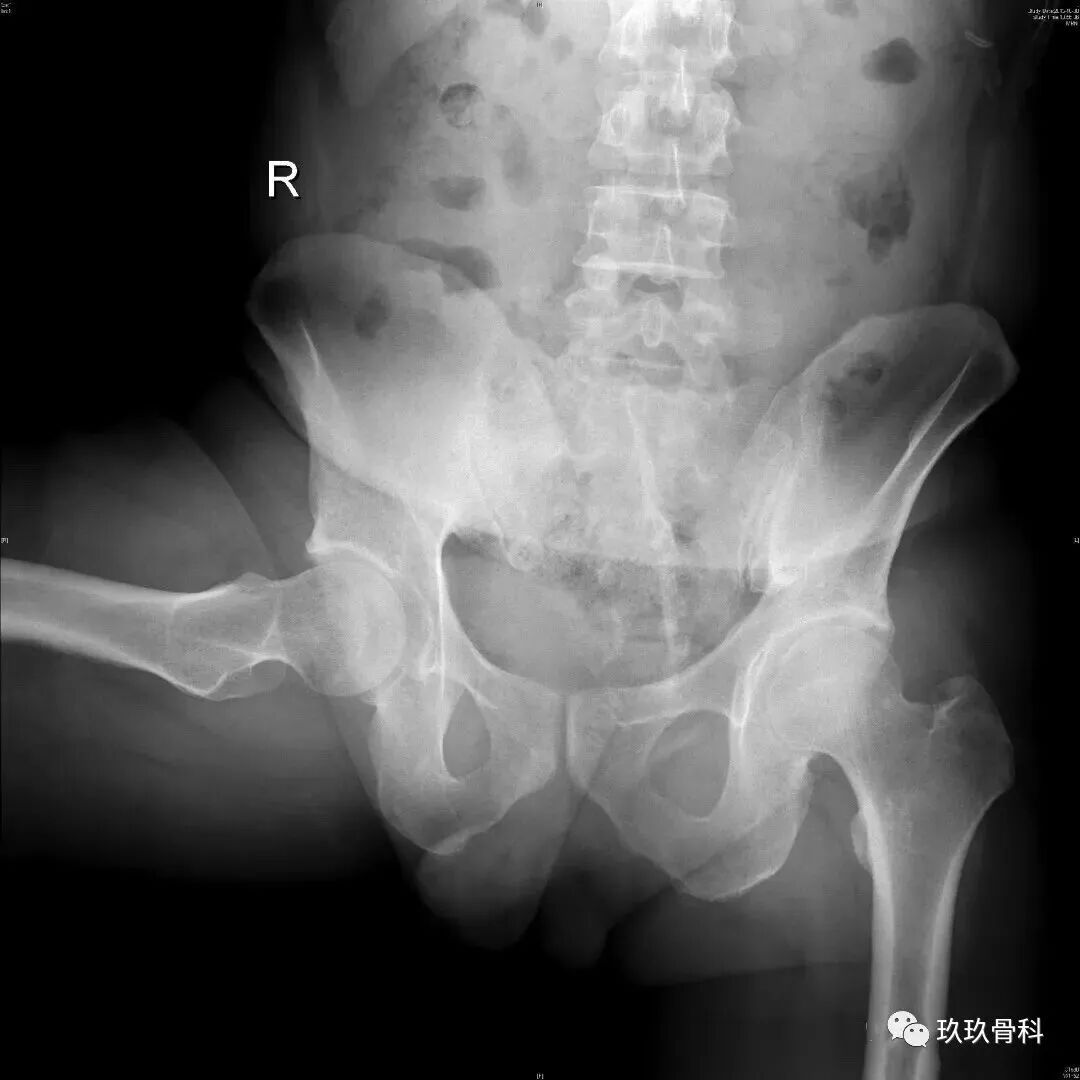

哪些情况需要做髋关节镜手术?

髋臼盂唇损伤,髋关节撞击综合症,髋关节游离体等,适合髋关节镜手术并且疗效确切。反复出现的不明原因髋痛,关节反复积液,滑膜病变,关节感染等也可以通过髋关节镜解决。年龄不是禁忌症,最多见的患者年龄为20-40岁,年轻的运动爱好者是主要的手术人群。中重度髋关节发育不良、明显的骨性关节炎等,长期疗效不佳,一般不建议关节镜手术。